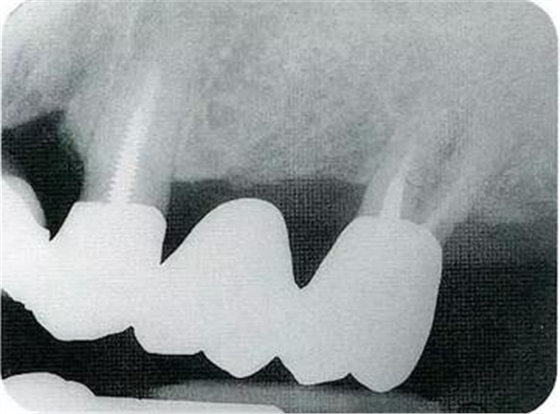

▼圖20-7

圖20-7最終修復(fù)完成后。

▼圖20-8

圖20-8最終修復(fù)完成經(jīng)過了12年后。